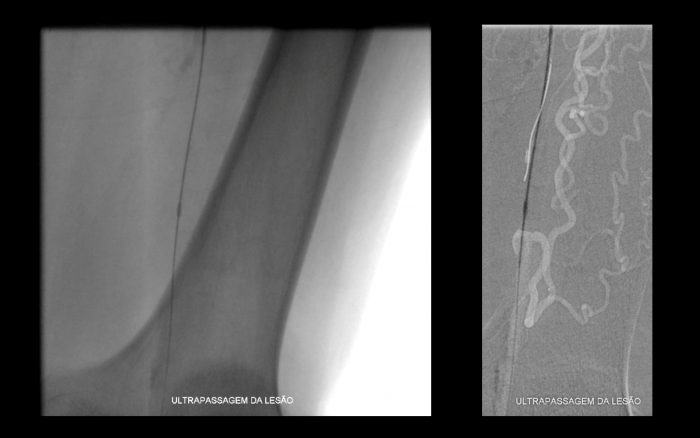

Paciente com história de claudicação dos membros inferiores para curtas distâncias, já submetido a angioplastia do membro inferior direito, retorna ao serviço com piora dos sintomas no lado esquerdo, sem lesão trófica (Rutherford 3)